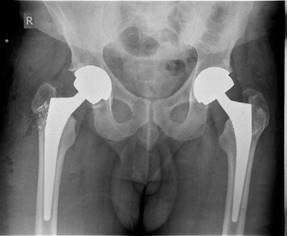

EXAMINER : These are the radiographs of a 78-year-old lady who has been referred to the orthopaedic clinic by her GP because of increasing pain in her right hip. Would you care to comment on the radiographs? (Figure 2.7.) CANDIDATE : This is an AP radiograph, demonstrating lower lumbar vertebrae, both hips and proximal femur. The most obvious features in the right hip are loss of joint space, osteophytes, sclerosis and bone cysts. The radiographic features are highly suggestive of osteoarthritis (OA) of the hip. EXAMINER : How is osteoarthritis classified? CANDIDATE : OA is classified into primary OA when obvious cause can be identified and secondary OA caused by such conditions as avascular necrosis, DDH, post traumatic, Pagetโs disease, slipped capital femoral epiphysis, protrusio acetabuli, Perthesโ disease. EXAMINER : What are the percentages of each type of OA? CANDIDATE : Various studies have suggested that almost 90% of cases of OA are secondary. EXAMINER : How are you going to manage this patient? CANDIDATE : I would take a full history and examination from the patient, specifically I would want to know the location of pain, exclude referred pain from the spine. Hip pain is

Figure 2.7 Anteroposterior (AP) radiograph demonstrating severe osteoarthritis of the left hip.